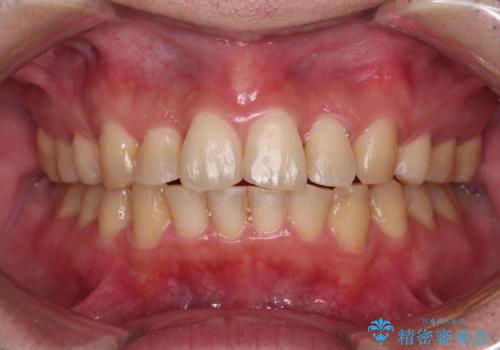

矯正歯科治療 → 叢生(でこぼこ・八重歯)

強い咬み込みですり減った前歯 デコボコを抜歯矯正で整える

ワイヤー矯正とオールセラミックの組み合わせ治療